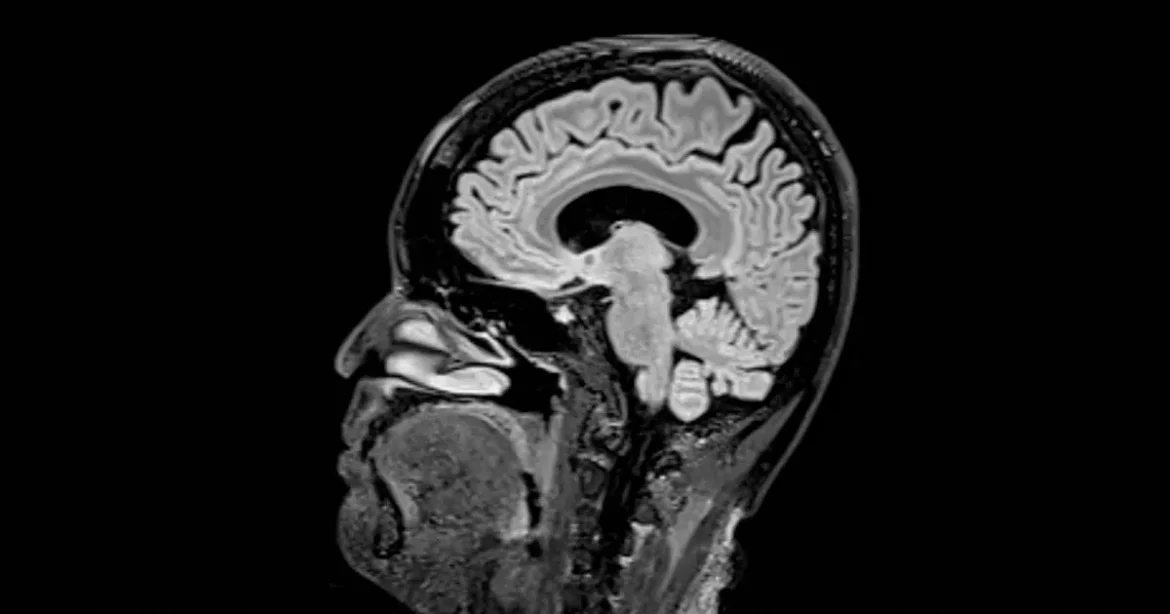

Agyunk fejlődési szakaszai

Brit és amerikai kutatók új tanulmányukban öt fő korszakra bontották az emberi agy fejlődését, amely szerint a felnőttkor 30 éves kor után kezdődik. Eredményeik arra engednek következtetni, hogy az agy még 83 évesen is új éra felé mozdul el. A kutatás részleteit a Nature Communications tudományos folyóiratban publikálták.

A tanulmány során a kutatók négyezer, 90 év alatti ember agyi idegi kapcsolatait vizsgálták, és ezen adatok alapján öt fontos fordulópontot azonosítottak: ezek körülbelül 9, 32, 66 és 83 éves korban következnek be, amikor az agy szerveződése új pályára áll.

Duncan Astle, a Cambridge Egyetem neuroinformatikusa elmondta, hogy az életünket valóban különböző fázisok határozzák meg, és úgy tűnik, hogy agyunk fejlődése is ezen fázisok mentén halad előre. Az agy strukturális fejlődése tehát nem egyenletes ütemű, hanem egyes jelentős események köré épül.

A gyermekkori fejlődés szakasza a születéstől 9 éves korig terjed, míg a serdülőkor átlagosan egészen 32 éves korig tart. A 30-as évek elejétől kezdve az agy ideghálózatai elérik a felnőttkort, ami több mint három évtizedig tart. A harmadik fordulópont 66 éves kor körül következik be, ami már a korai öregedés szakasza, míg a késői öregedés tűnik fel körülbelül 83 évesen.

A kutatás során az agy szerveződését 12 különböző mutató alapján mérték, beleértve az ideghálózat hatékonyságát és struktúráját, illetve azt, hogy az agy mennyire támaszkodik központi csomópontokra, vagy inkább egy szétterjedt kapcsolati hálóra. A csecsemőkortól a gyerekkoron át az agy fejlődését a hálózati konszolidáció jellemzi, amikor a szinapszisok száma csökken, és csak a legaktívabb kapcsolatok maradnak fenn. Ezen időszak alatt a szürke- és fehérállomány térfogata növekszik.